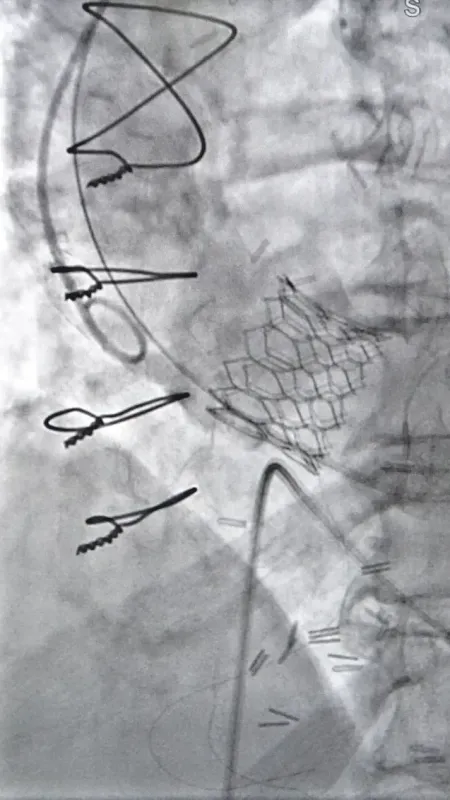

Kalp ve Damar Cerrahisi'nden Dr. Öğretim Üyesi Tuncay Erden'in muayenesi sonrası oluşturulan heyet, Tsutsunava'nın aort kapağında ileri derecede daralma tespit etti ve kapalı yöntemle aort kapağı değiştirme kararı aldı. Kardiyoloji Uzmanı Doç. Dr. Zeydin Acar'ın katılımıyla gerçekleştirilen operasyon, yaklaşık 1 saat sürdü ve başarılı bir şekilde tamamlandı. Üç gün sonra taburcu edilen Nunu Tsutsunava, sağlığına kavuşmanın mutluluğunu yaşadı.

Gürcistan'dan gelen hasta için yapılan operasyonu anlatan Kardiyoloji Uzmanı Doç. Dr. Zeydin Acar, hastanın tekrar göğsünü açarak ameliyat etmenin zor olduğunu belirterek, "Hastamız nefes darlığıyla bize başvurdu. Daha önce bypass olduğu için tekrar açık ameliyat yapmak riskliydi. Bu yüzden kapalı yöntemle kapak yerleştirmeyi uygun gördük. Yaklaşık bir saatlik bir operasyonla aort kapağını değiştirdik. Bugün üçüncü günümüzde ve hastamızı taburcu ediyoruz" dedi.